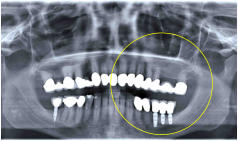

Implantate mit Aufbau für Kronen

mit Kronen versorgte Implantate